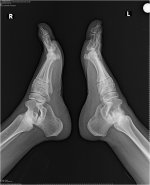

اعاني من الام في منطقة الكعب وخصوصا في القدم اليمنى عند الاستيقاظ من النوم او الجلوس لفترة ثم القيام او المشي لفترة طويلة مع العلم ان هذا الالم بدا منذ اربعة اشهر تقريبا وقمت بعمل عدة تحليلات وفحوصات كما تناولت حبوب فولترين 100ملج لمد عشرة ايام بوصفة طبية ولم يزل الالم بالاضافة انني اداوم على تمرينات القدم

• hh.jpg

hh.jpg

حضرتك تعانين من التهاب في وتر اكيليس وهو الوتر الواصل ما بين عضلة السمانة وباطن القدم. هناك بعض النصائح ستساعد على تخفيف الالام ان شاء الله مثل استخدام كمادات ثلج على باطن القدم واسفل عضلة السمانة ليلا. عمل تمارين اطالة لعضلة السمانة خاصة عند الجلوس فترات طويلة استخدام الدهانات الموضعية المضادة لاالتهاب والمسكنة مثل الفولتارين والروفيناك. لا انصحك باستخدام اقراص الفولتارين المسكنة بصورة مستمرة لخطورتها على الكلى. يمكنك استخدام بانادول اقراص بشكل منتظم حتى يتحسن الالم. تمنياتي بالشفاء العاجل